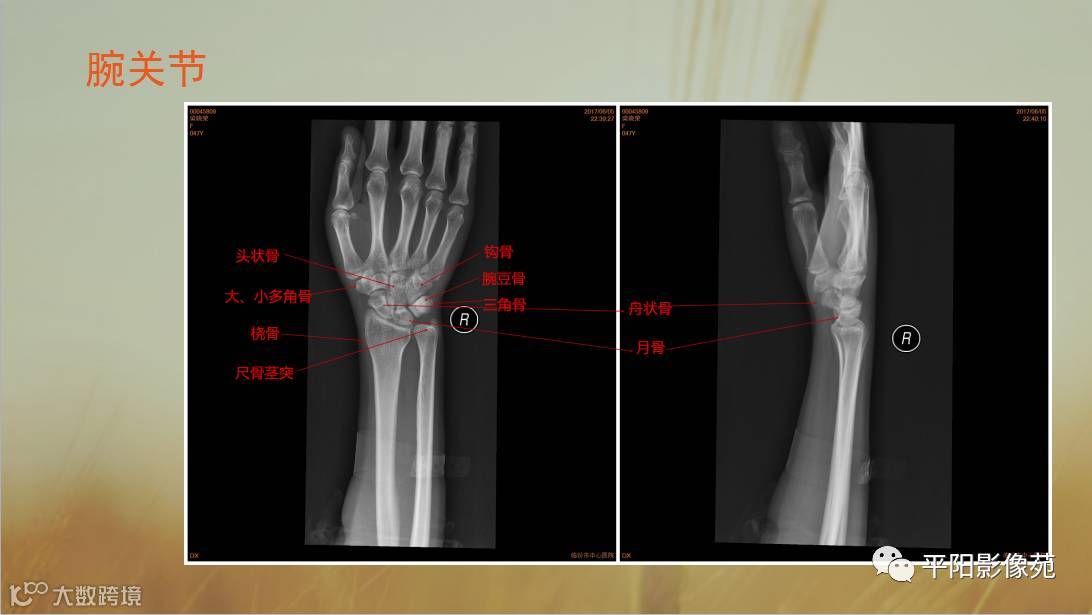

四肢骨骼X线解剖